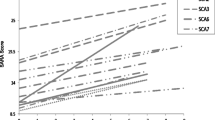

A total of 126 SCA3 patients (with CAG repeats ranging in number from 58 to 85) and 41 HCs (CAG repeats from 13 to 43) were included in this study. SCA3 patients and HCs were matched for age, sex, and years of education. Among the SCA3 patients, 76.2% were symptomatic and 23.8% were pre-symptomatic. Demographic, clinical, and genetic characteristics are presented in Table 1.

In general, 30.8% (37 patients) of the 120 fully evaluated SCA3 patients were defined as CI; the other 69.2% SCA3 patients were defined as CP. Compared to the CP subgroup, the CI subgroup was older and had later onset, lower education level, and longer disease duration; the CI subgroup also had higher SARA and ICARS scores and had a higher proportion of motor symptom involvement (all P < 0.05). Notably, only one of the CI subgroup patients was defined as pre-symptomatic; the other 36 patients were defined as symptomatic. No differences were found in sex or the number of CAG repeats between the CI and CP subgroups (Table 2).

The most frequently impaired cognitive domain detected for the SCA3 patients of our cohort was information processing speed, followed by verbal memory, executive function, and visuospatial perception. SCA3 patients defined as cognitively impaired (CI) had longer disease duration, a lower level of education, and more severe motor function impairment compared to those defined as cognitively preserved (CP). Our MRI data enabled VBM and ROI analyses, which revealed that volume loss in segmented cerebellar lobules (bilateral lobule VI, right lobule Crus I, and right lobule IV, and especially left lobule VI) contributed to cognitive impairments in SCA3.

Previous meta-analysis of neuroimaging studies reported that lesions to different cerebellar structures/regions affect distinct neurological functions: the anterior lobe (lobules I–IV) and the lobule VIII are engaged during overt movements, whereas posterior and lateral cerebellar regions (lobules VI, VII, Crus I, and Crus II) are active during cognitive tasks [44, 45]. Few studies have employed volumetric neuroimaging to assess cerebellum–motor function associations or cerebellum–cognition associations in SCA3 patients [21, 46]. One study (n = 32) reported that the right cerebellar tonsil was associated with abstract reasoning ability (with decreased scores in Raven’s progressive matrices) [21]; and a study including 5 SCA3 patients reported impaired adaptive motor learning was associated with lower volumes in the right cerebellar lobule VI and left cerebellar Crus I [46]. We used VBM- and ROI-based approaches to evaluate cerebellar lobule volume loss in the CI subgroup, and found that lower volumes in the bilateral lobules VI, right lobule Crus I, and right lobule IV were associated with cognitive impairments.

Beyond SCA3, the associations observed between cerebellum and cognition are common in other cerebellar diseases. Previous studies examining SCA2 patients reported that cerebellar volume loss in lobules VI and Crus I correlated with visuospatial, verbal memory and executive function [47, 48]. In patients with Friedreich’s ataxia (n = 22), structural and functional MRI data showed that the cerebellum lobules VI and Crus I were associated with verbal fluency (executive functioning) [49]. Additionally, studies of other neurodegenerative diseases have demonstrated cerebellar atrophy as a risk factor for disease progression and implicated cerebellar atrophy in cognitive dysfunction [11, 12, 50]. A study examining 53 patients with Alzheimer’s disease reported that atrophy degree in cerebellar lobules VI and Crus I was positively correlated with praxis ability (with decreased scores for copying drawings) [51]. Similarly, studies of multiple sclerosis patients reported that atrophy degree in cerebellar lobules VI, left Crus I, and right VII was associated with information processing speed impairment [52, 53]. In Parkinson’s disease, atrophy degree in cerebellar lobules of bilateral lobules Crus I and left VI was associated with executive function impairment [54]. In familial frontotemporal dementia, cerebellar atrophy was observed in lobules VI and Crus I bilaterally, which were associated with impaired cognitive domains including attention, language, and executive function [55]. Notably, these studies and ours all implicate cerebellar lobules VI and Crus I in cognitive dysfunction in neurodegenerative diseases. Recent intervention studies have utilized both repetitive transcranial magnetic stimulation (rTMS) and transcranial direct current stimulation (tDCS) to address neurodegenerative diseases, reporting improvements in cognitive function [6, 56,57,58]. Of particular interest is the observation that modeling studies investigating cerebellar tDCS indicate the highest electric field strengths are centered in Crus I/II, a region associated with cognitive function [59, 60]. These intriguing findings suggest that using rTMS and tDCS to target cerebellar lobules VI and Crus I could confer benefit for SCA3 patients, and should potentially be explored in clinical trials.

Still, it is worth noting that cerebellar atrophy leading to cognitive impairment is not applicable to all cerebellar disorders. For instance, patients with SCA6, where volume loss in lobule VI was identified [61], are often absent of cognitive decline in attention, and executive function [62]. A study utilizing the CCAS scale to assess 30 SCA3 and 14 SCA6 patients reported significant abnormalities in SCA3 but not in SCA6 [31] given that the brain is highly interconnected networks and remarkable capacity for neuroplasticity [63]. For SCA3 and other hereditary ataxias, factors such as the specific genetic mutation, and interactions with brain regions play a complex role in determining the cognitive function.